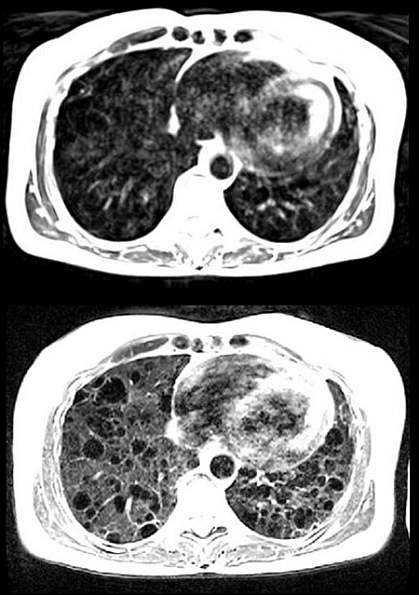

The team also compared lung images taken in patients with lymphangioleiomyomatosis, a rare disease that creates cysts in the lung. Images of the cysts and the surrounding tissue taken with the lower magnetic field were clearer than those taken at 1.5 T. The system not only improved lung imaging, but also was more sensitive to changes in image contrast caused by oxygen, providing a unique view of the distribution of this vital molecule in the body.